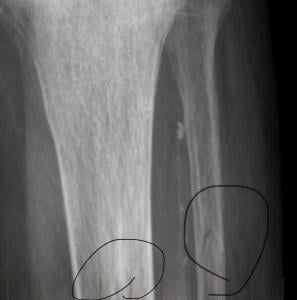

I live near Ann Arbor, Michigan, so I researched orthopedic oncologists at the University of Michigan Hospital. It didn’t take long for me to find the head of that department, so I reached out and requested an appointment with her. At my first oncology appointment, she told me that I had a fractured tibia and a fractured fibula, and that I would need a bone biopsy. Within days, she scheduled a hospital stay to determine exactly what my situation was. It was the week of my birthday, May 17. I felt restless, and the uncertainty felt like a knot in my gut.

I remember that after the biopsy, she walked into my room and said, “Mr. Shelton, the bone biopsy showed that you have prostate cancer in your left leg.” My family and friends know that I’m a big joker, so I chuckled, waiting for the punchline. However, there was no punchline. When I asked for clarification, she told me that a “prostate cell looks like 1 thing, a prostate cell. That’s what we found in your tibia.” A subsequent PET scan and a bone scan further revealed that nearly all of the cancer had moved from my prostate gland into my left leg, with tumors from mid-thigh to my ankle (see image above).